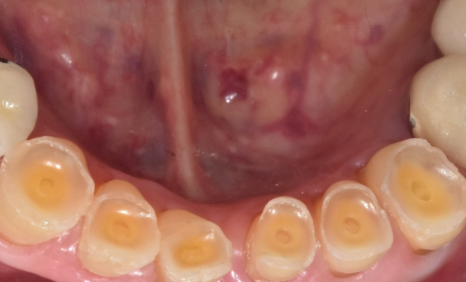

다행히 이 아래 앞니들은 흔들림이 크지 않아

뿌리가 버텨주는 상태였기 때문에,

신경치료를 먼저 진행한 뒤

크라운으로 씌워 높이를 다시 세워 주었습니다.